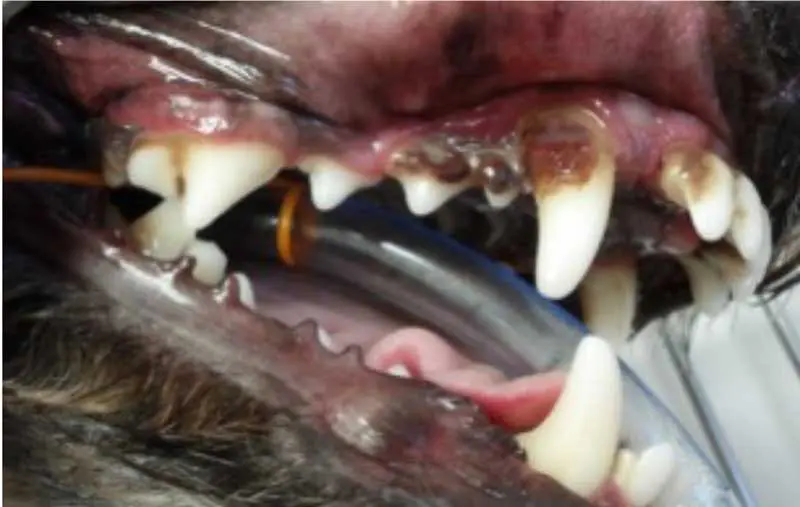

Stage 2 – early periodontitis

At stage 2, the inflammation extends below the gum line, affecting the supporting structures of the teeth (Figure 4). Osteolysis can be radiographically noticeable, with up to 25% bone loss.

Symptoms of early periodontitis may include:

- Noticeable tartar buildup.

- Mild tooth mobility (single-rooted teeth).

- Halitosis.

- Bleeding when the dog eats or chews.

Stage 3 – moderate periodontitis

The attachment loss continues to progress, with 25% to 50% bone loss. Periodontal pockets form between the teeth and gingiva, and furcation of the teeth becomes exposed, harbouring bacteria and leading to further damage (Figure 5).

Stage 4 – advanced periodontitis

In the advanced stage of periodontal disease, bone loss exceeds 50%. At this point, tooth loss is common due to the loss of the alveolar bone and periodontal ligament. The patient may experience significant pain and discomfort (Figure 6).